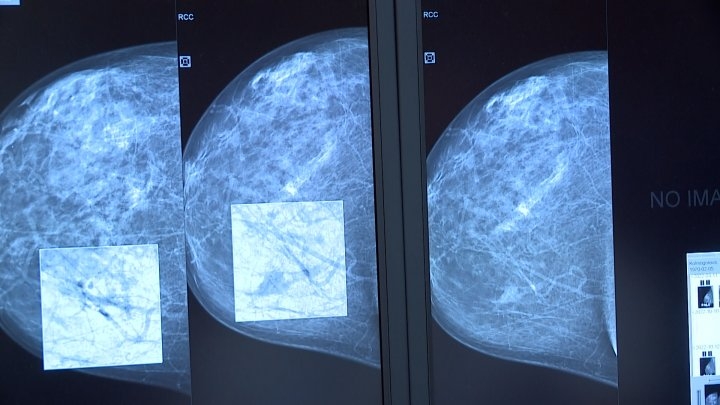

Что такое маммография: важность, процесс и результаты

Раздел: Необычные решения